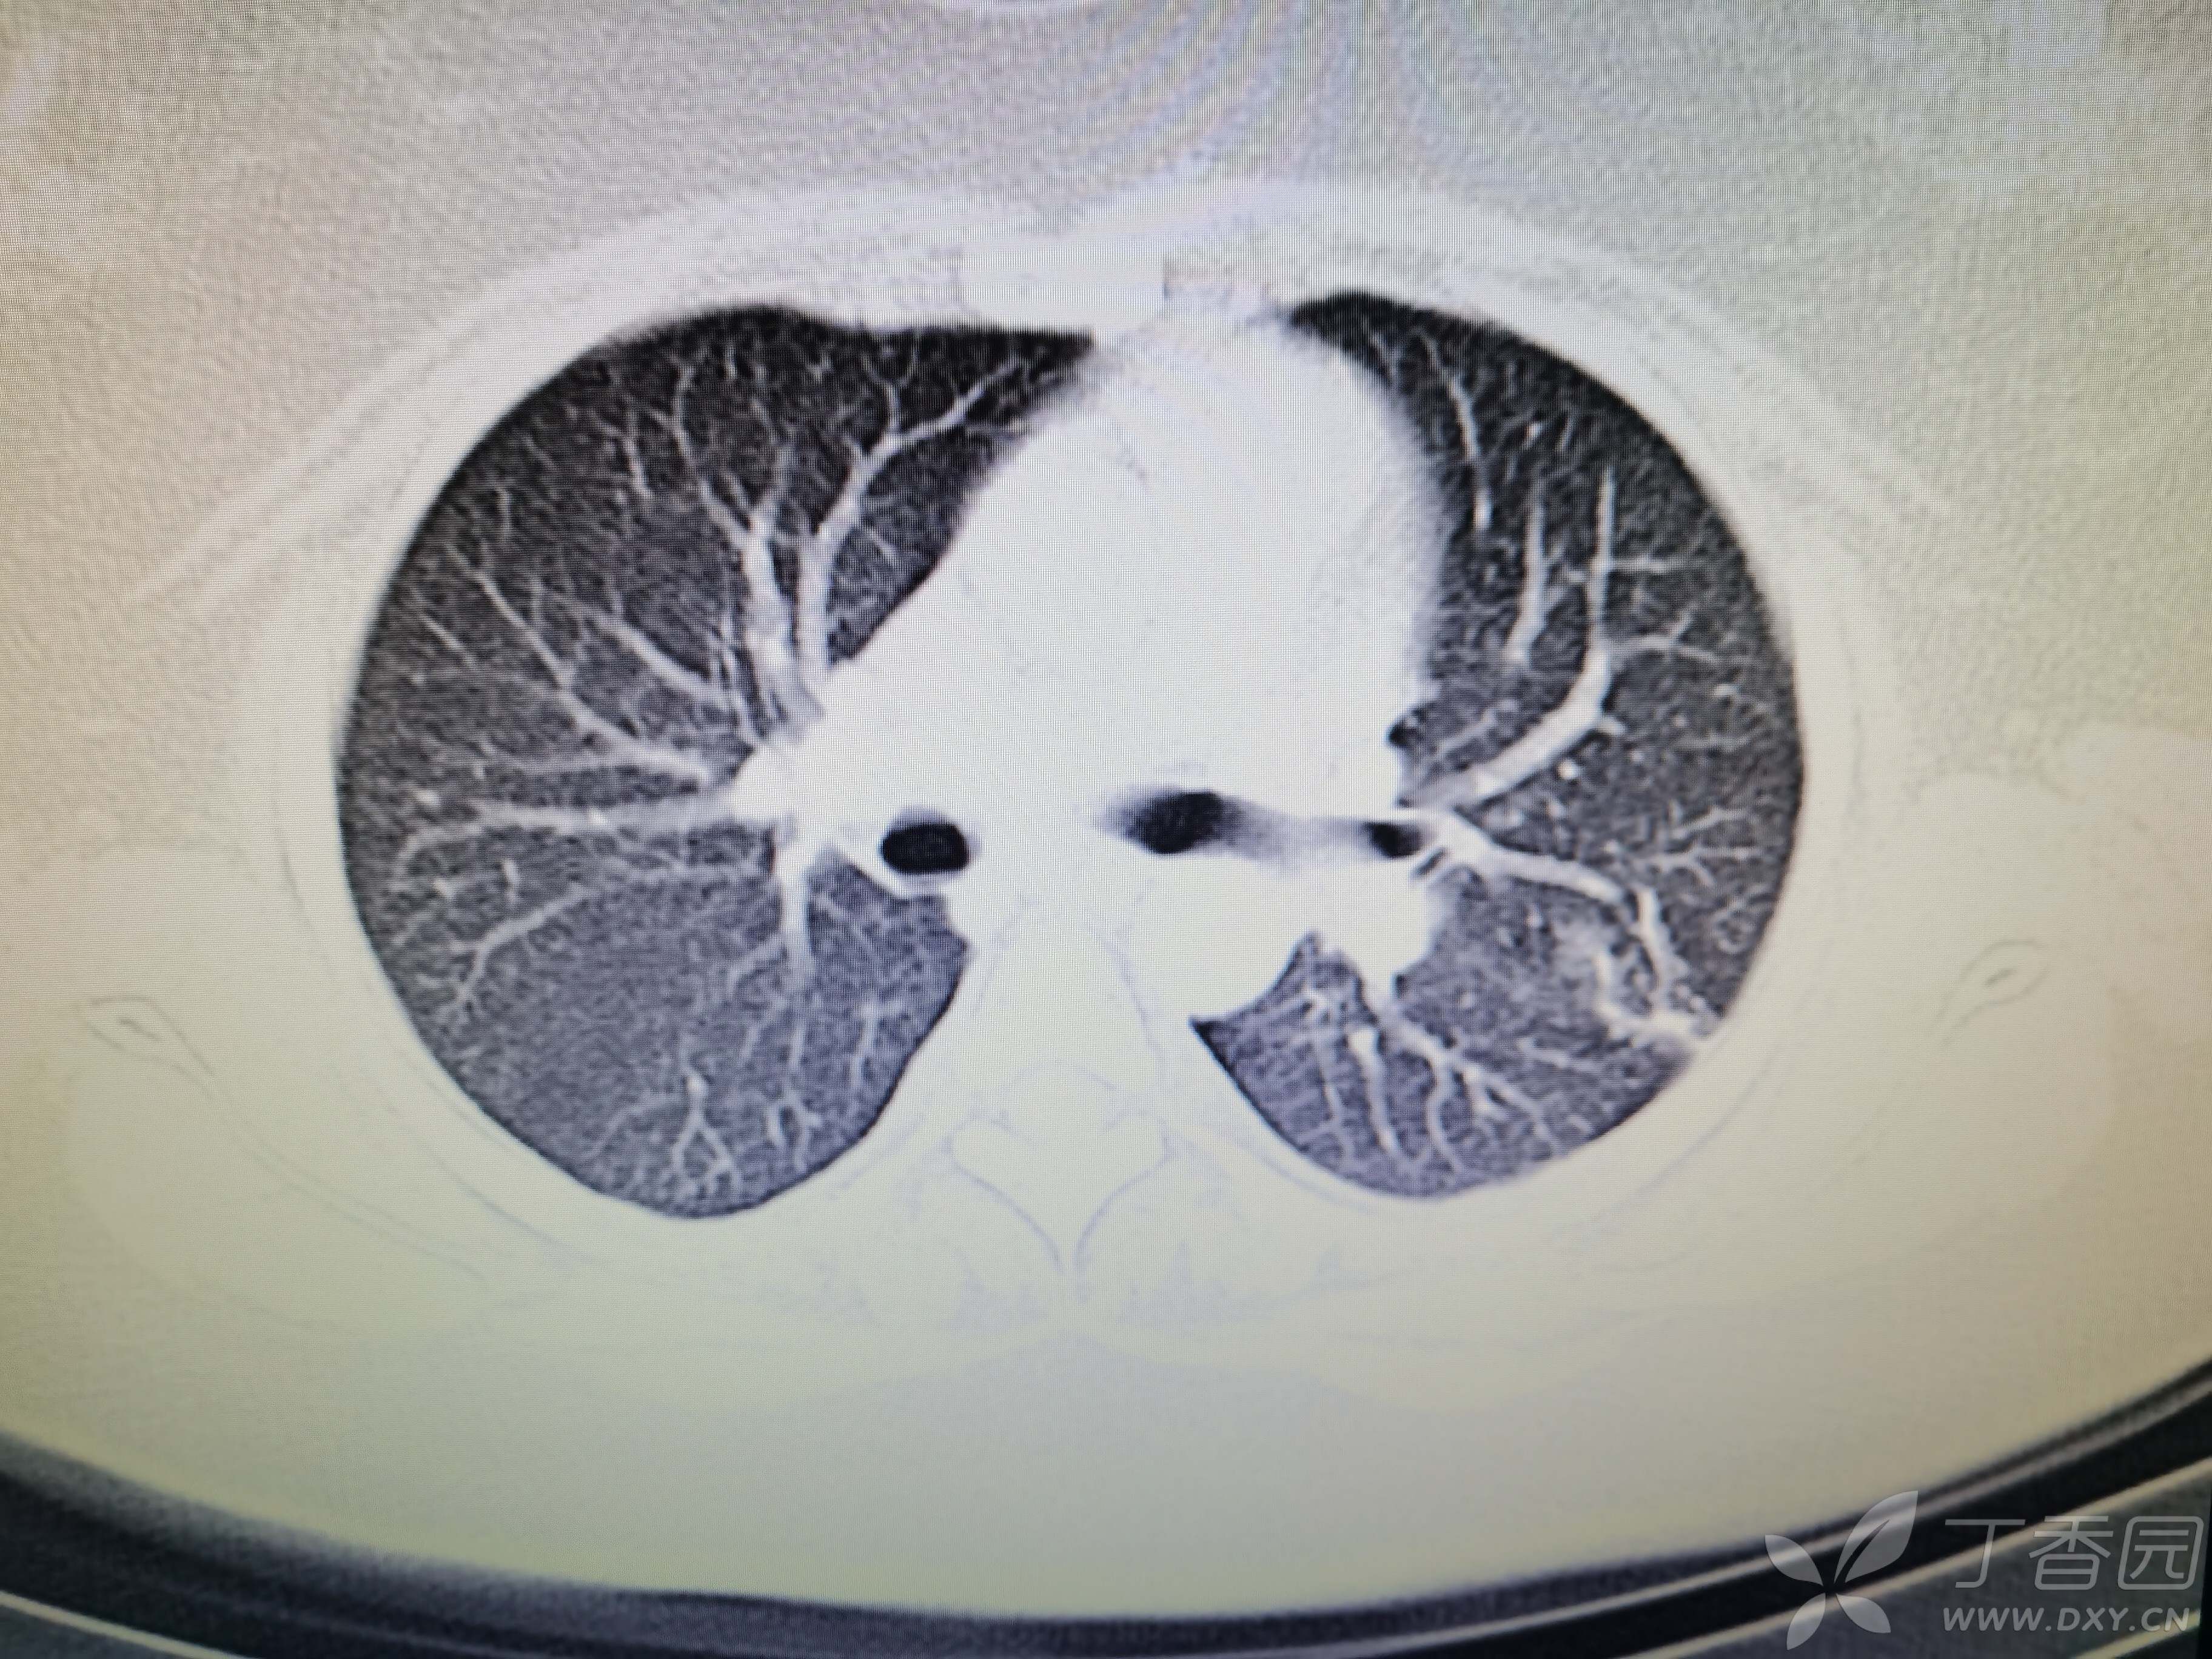

基本信息:女,三十几岁,印度人。。

胸部CT:

如题:猜肺部病灶病理。。